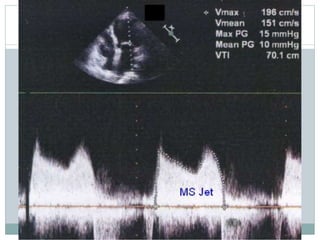

PRESSURE GRADIENT

 Apical window

 CWD /PWD at or after tip of mitral valve

 Maximal and mean gradient

 Bernoulli equation( P =4V2)

 Derived from transmitral velocity flow curve

 Heart rate to be mentioned

 CD to identify eccentric mitral jet

 Maximal gradient influenced by LA compliance and

LV diastolic function

 In AF average of 5 cycles with least variation of R-R

interval and as close possible to normal HR

 MVG dependent on HR,COP and associated MR

 Tachycardia, increased COP and associated MR

overestimates gradient

 Maximal gradient is markedly affected